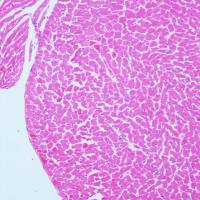

EVG染色样片参考:

弹性纤维呈蓝黑色;胶原纤维呈红色;背景呈淡黄色。